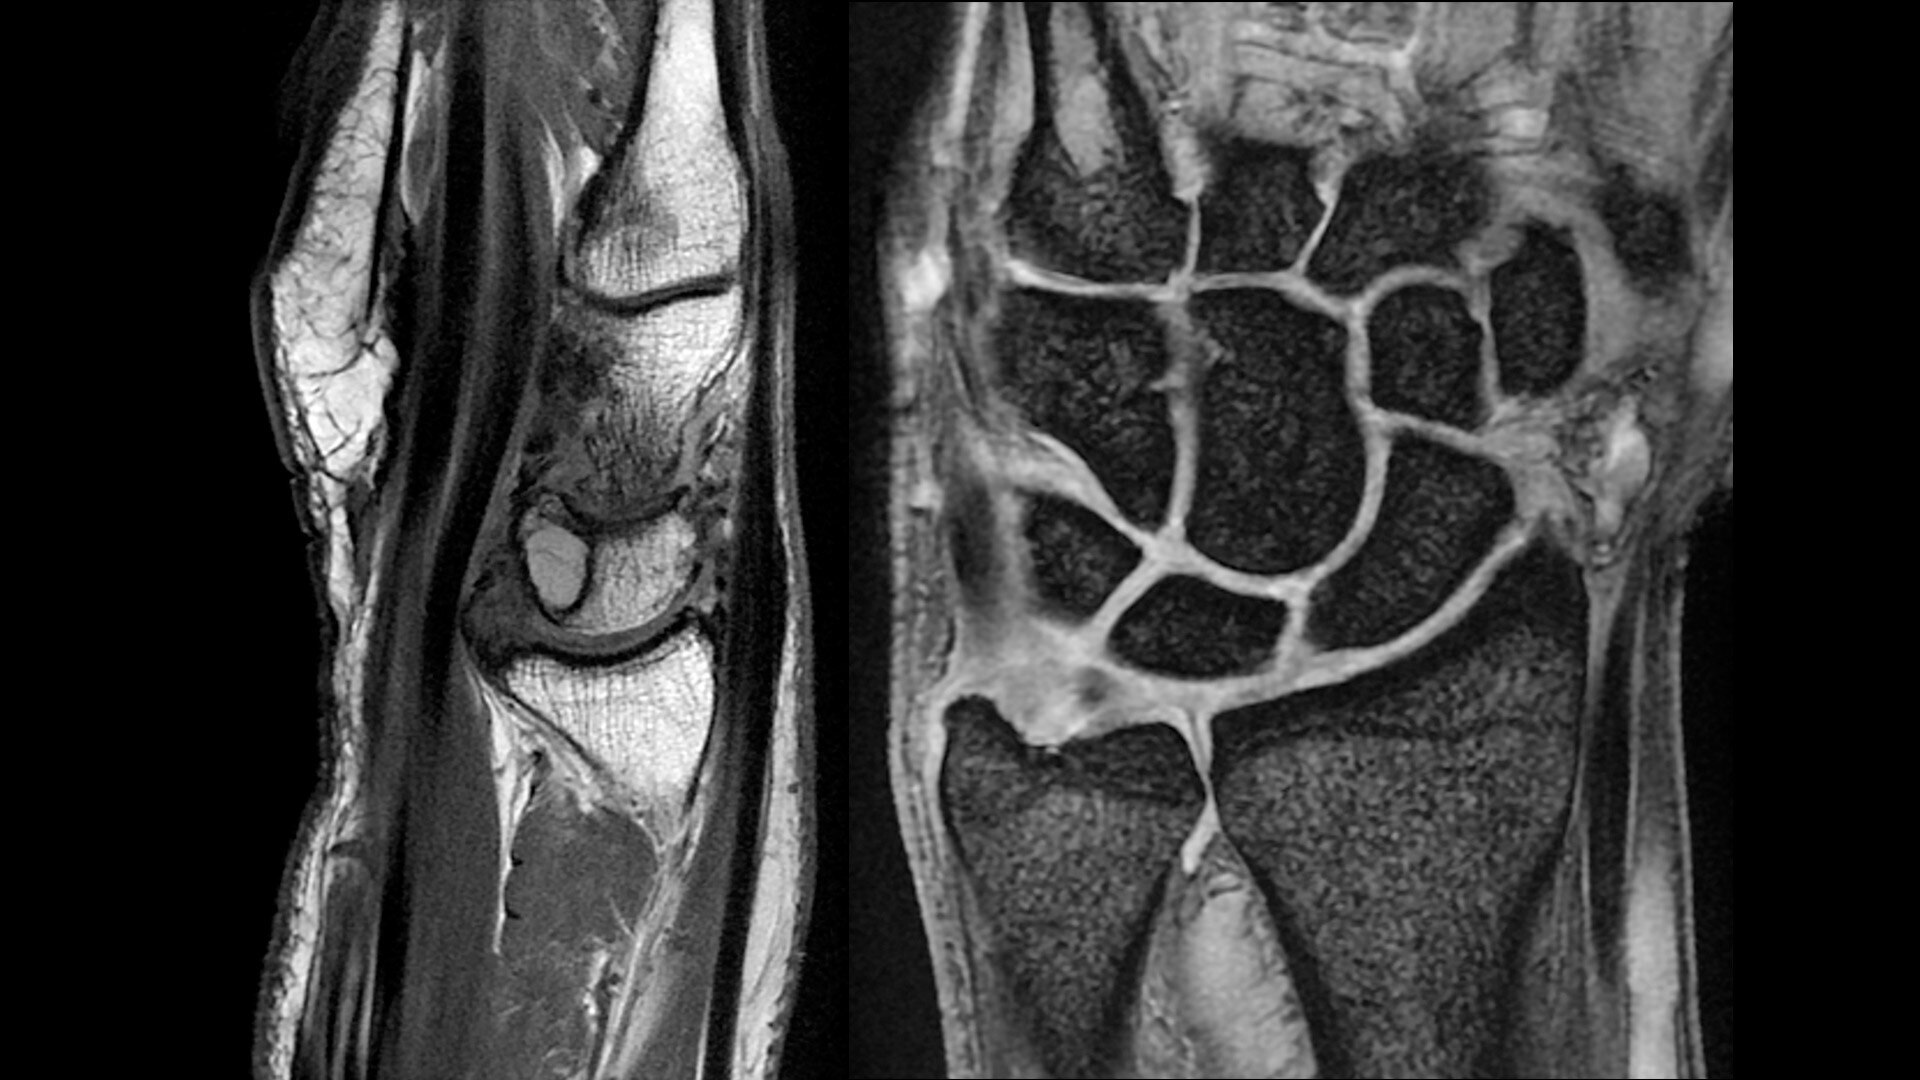

The shape of the MRI coil no longer determines what you can do with it. Wrap it around a knee for a complete knee image. Drape it over the patient's body. With an adaptive AIR™ Coil that is light, form fitting and easy to position, it’s the closest you can get to total positioning freedom with 360-degree coverage.

AIRTM MULTI-PURPOSE COILS

• 360 degrees of coverage for MSK imaging

• 38% lighter per channel compared to previous generations of conventional coil technology

• Increased acceleration compared to previous generations of conventional coil technology

• Positioning freedom with previously hard-to-scan anatomies

• 20-ch and 21-ch design to accommodate all patient sizes and anatomies